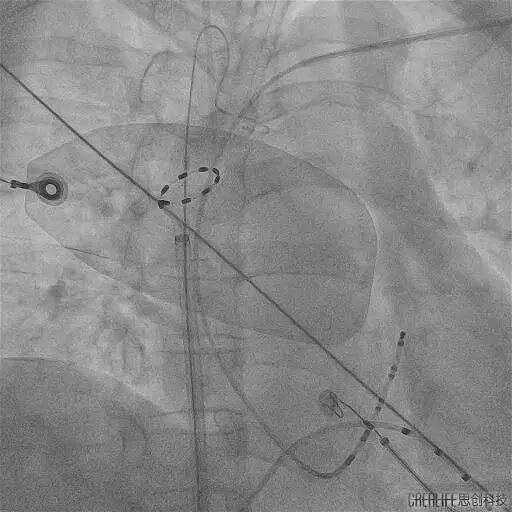

PS导管通过外鞘送入左心房,在二维引导下到达目标肺静脉,在导丝指引下调整导管成环进入肺静脉,使环形电极贴靠肺静脉口/前庭。

观察电极形变并明确电位,确认贴靠良好后依次对每个每支静脉进行口部4次+前庭6-8次的脉冲消融,对上腔静脉补充4次消融,完成四根肺静脉(PVI)和上腔静脉的环形隔离。

PS导管行LSPV消融

PS导管行LIPV消融

PS导管行RSPV消融

PS导管行RIPV消融

PS导管行SVC消融